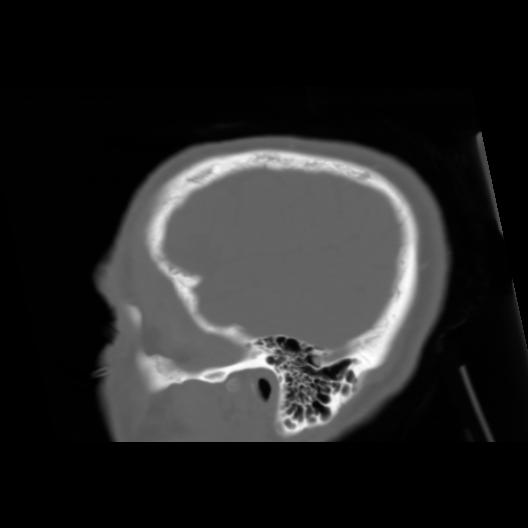

6 CEREBRO,,Sagittal,3.000,CEREBRO,Sagittal,